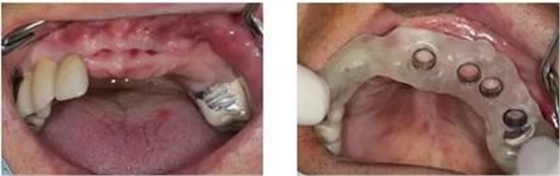

將種植方案數(shù)據(jù)打印成數(shù)字化導(dǎo)板

根據(jù)導(dǎo)板孔徑種牙,精準(zhǔn)、微創(chuàng)、不翻瓣

方便“即刻種植”

根據(jù)術(shù)前的方案規(guī)劃和術(shù)中導(dǎo)板的精確定位,拔牙和種植可在一次手術(shù)中完成。

即刻修復(fù)”成為可能

根據(jù)術(shù)前確定的種植方案制備臨時(shí)修復(fù)義齒,手術(shù)過(guò)程中種植和修復(fù)一次完成。